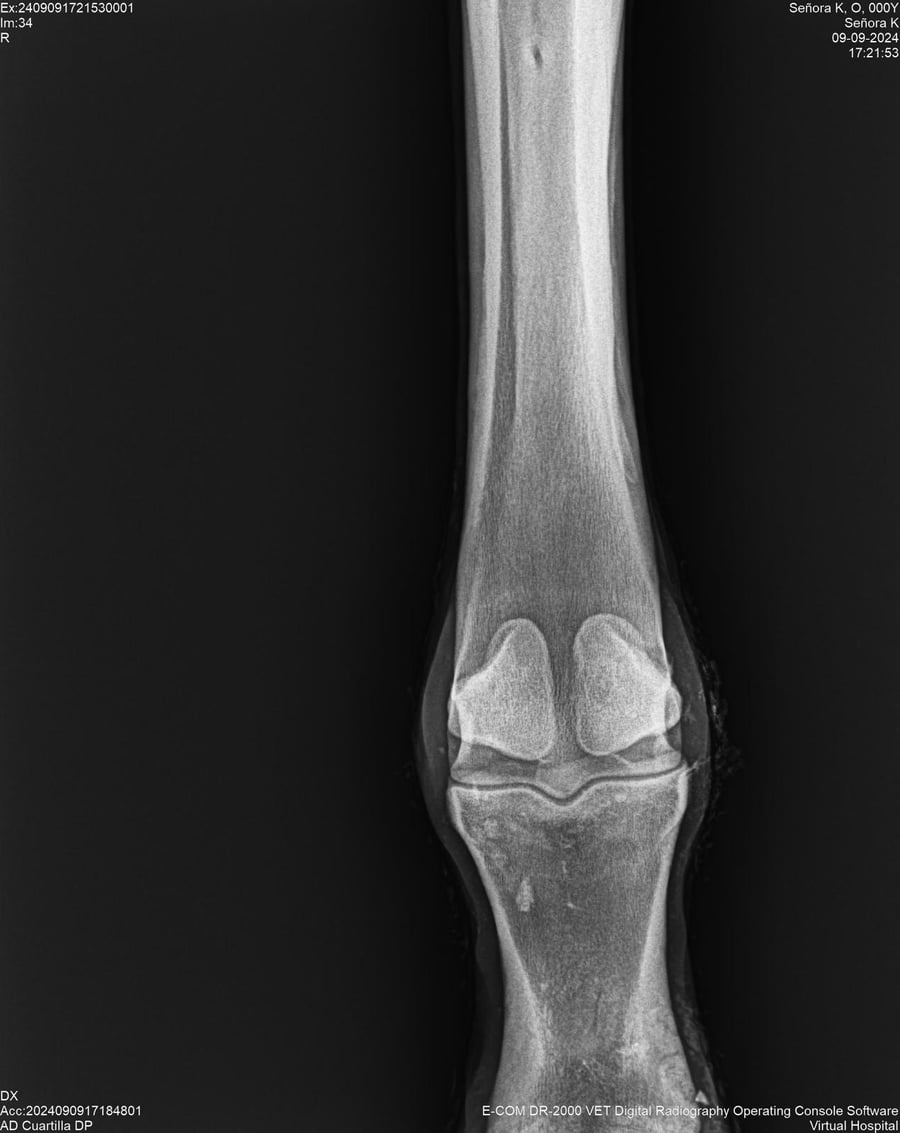

LOTE 44, SEÑORA K

Identificador: #291147-

Generacion 2022